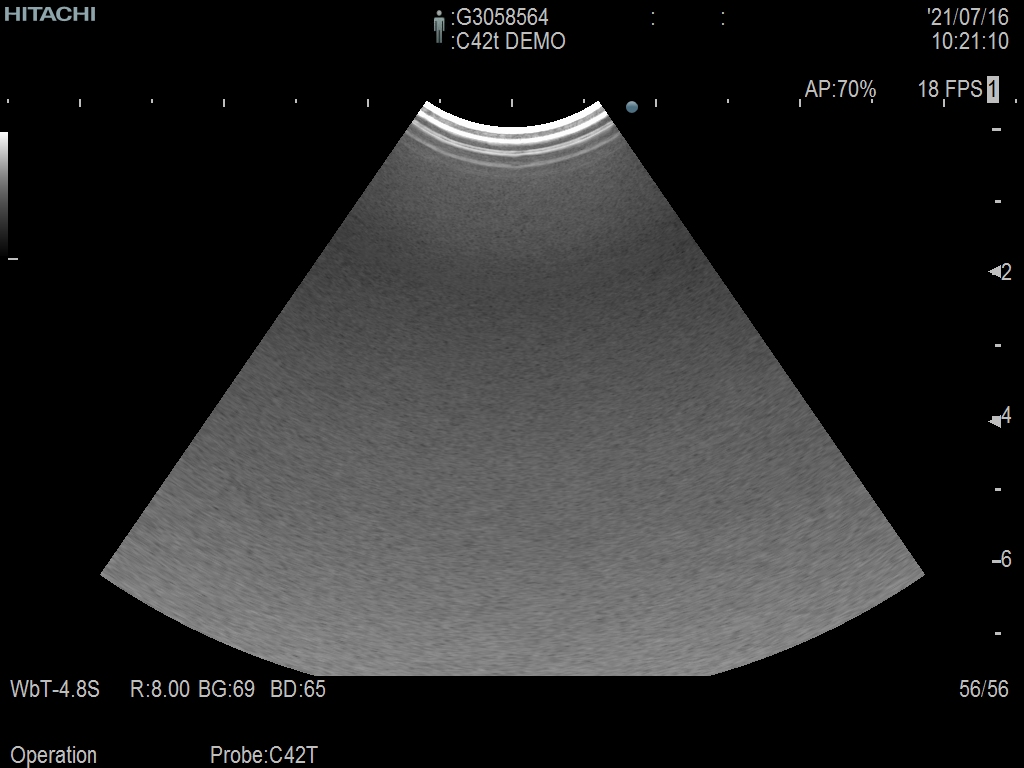

Hitachi C42T Ref Intraoperative Convex – ARIETTA

ARIETTA Convex C42T Intraoperative

Intraoperative Finger-grip T-Style

10 – 3 MHz

Hitachi C42T Intraoperative Convex – ARIETTA

Frequency Range: 10 – 3 MHz

Scan Width: 20 mm Radius

Scan Angle: 65° FOV

Hitachi C42T Intraoperative Convex – ARIETTA for Intraoperative Finger-grip Convex T-Style